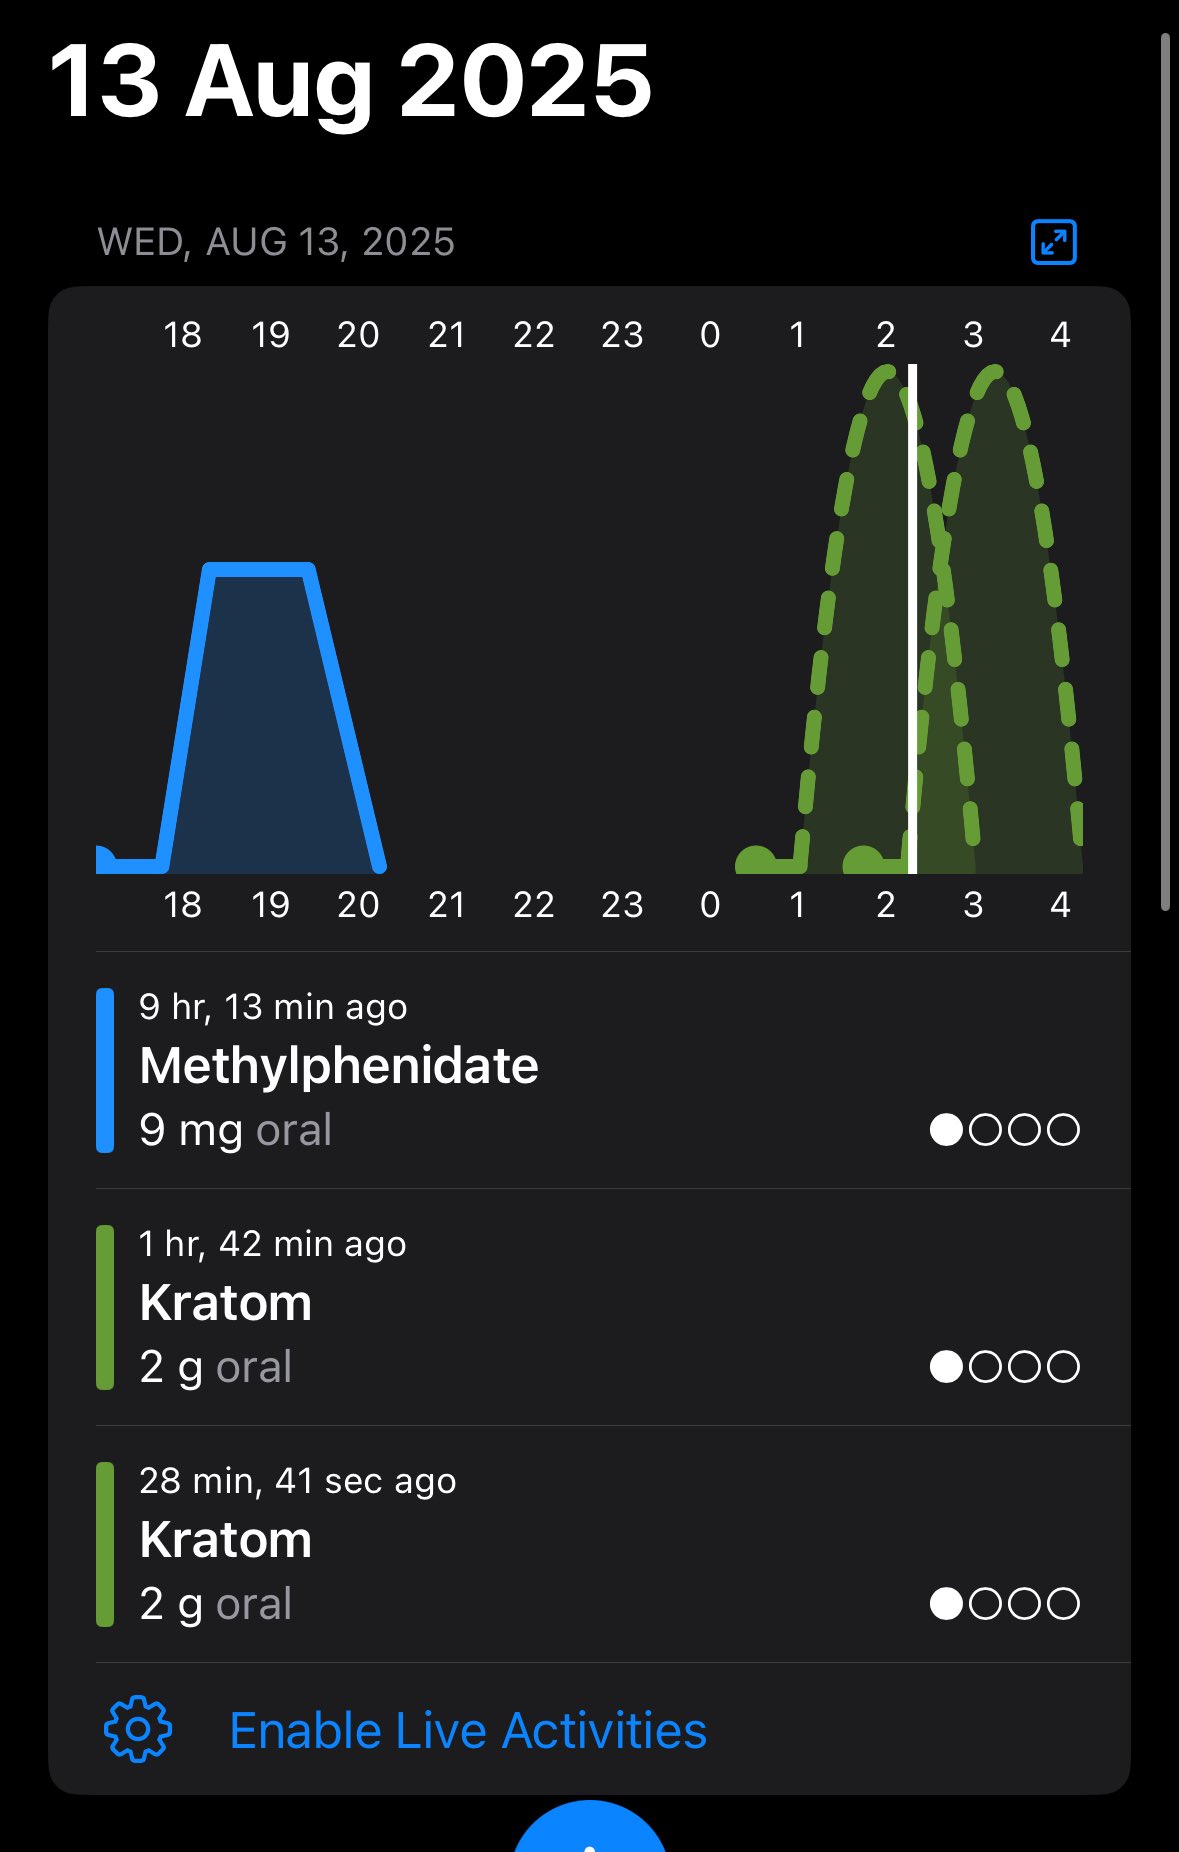

2024-08-14 11:34:53 UTC

甚至在第二天有余晖的感觉,虽然发生了很多破事但没怎么影响心情*抗焦虑&镇静

运动协调性稍差,表现为走路和站立时平衡不好

此剂量下对睡眠的改善作用,增加了慢波睡眠且没有影响rem,精力恢复+

FDA数据,在临床剂量下(75-600mg)普瑞巴林的依赖性低于bzd,并相比之下它产生的认知和精神运动障碍较轻 https://t.co/TJ7ZOQ7pbC